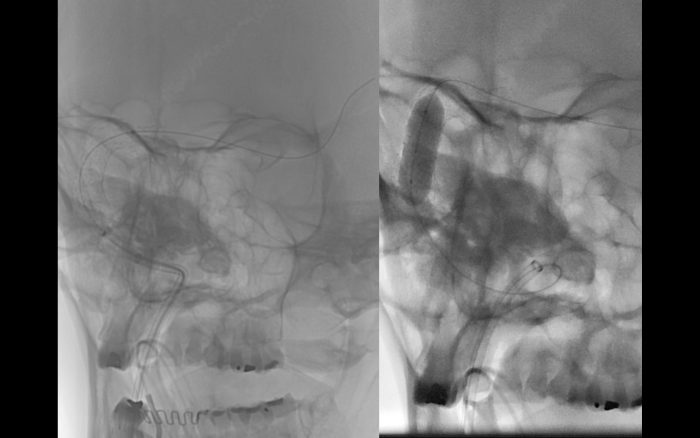

O caso ilustrado é de uma paciente de 33 anos com papiledema, cefaleia intensa, zumbido e perda progressiva do campo visual. Foram realizadas aferioções da pressão em todo trajeto do seio transverso e sigmoide direito, sendo evidenciado diferença de pressão de 10 mm/Hg relacionada ao ponto de estenose. Após o diagnóstico, foi instituído o tratamento por angioplastia com Stent (Precise – Cordis), devido sua facilidade de navegação e acomodação em tortuosidades. O procedimento transcorreu sem intercorrências, havendo resolução completa dos sintomas após 30 dias.